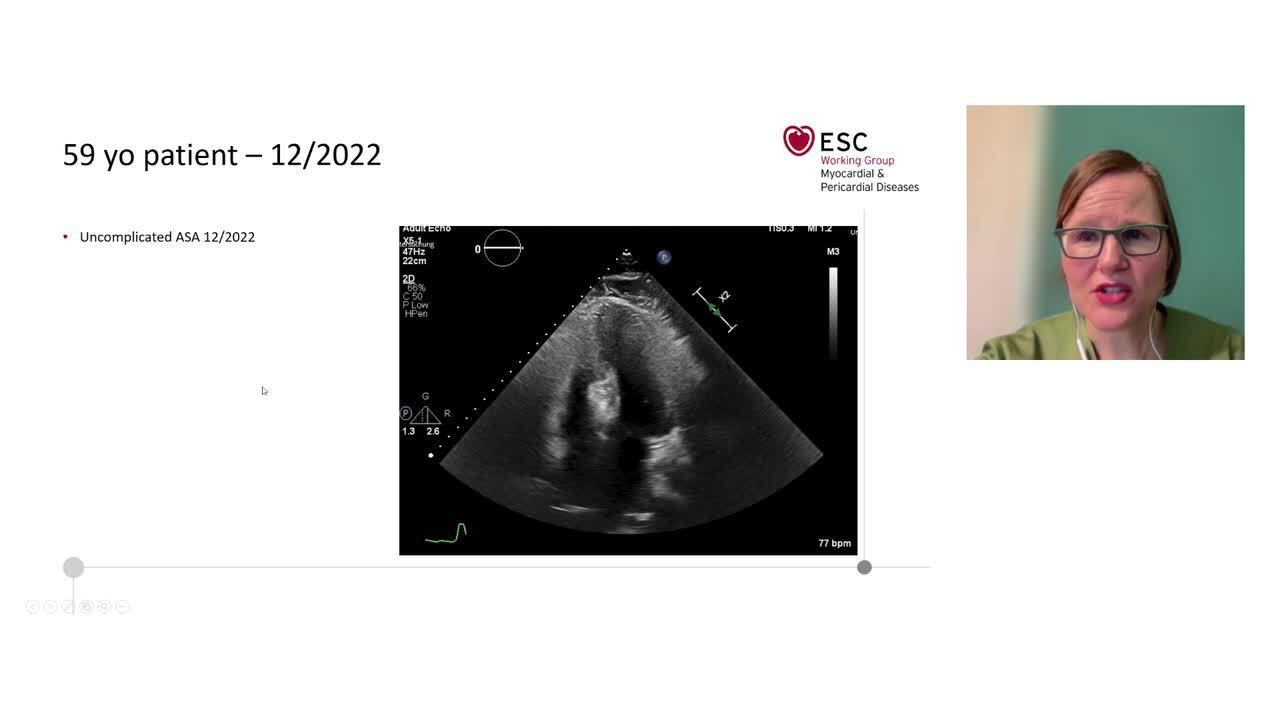

Hypertrophic cardiomyopathy: perspectives of the specialist and non-specialist in a healthcare environment

Webinar

7 Apr 2023 - 20:00